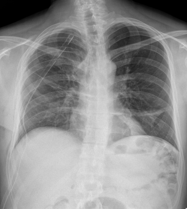

âȘ Table 5: We visualize samples of the generated reports for three cases. We bold the identical descriptions, underline the additional identified findings, and in red the failure findings..

X-ray Image | Baseline | M2TR | R2Gen | Ours |

![]() |

Pneumothorax gauche de moyenne abondance./Silhouette cardiaque dâaspect normal./Absence dâanomalie mĂ©diastinale./Absence dâĂ©panchement pleural./Absence dâanomalie du gril costal./ | Pneumothorax gauche de grande abondance./Contours cardiaques rĂ©guliers./MĂ©diastin sans anomalies dĂ©celables./ Aucun Ă©panchement pleural dĂ©tectĂ©./Structure du gril costal normale. | Pneumothorax de petite abondance./Aucune anomalie visible au niveau du mĂ©diastin./Pas de prĂ©sence d'Ă©panchement pleural./ | Pneumothorax bilatĂ©ral de moyenne abondance./Configuration normale de la silhouette cardiaque./MĂ©diastin clair, sans irrĂ©gularitĂ©s./Absence d'Ă©panchement pleural./Aucune lĂ©sion du gril costal observĂ©e./ |